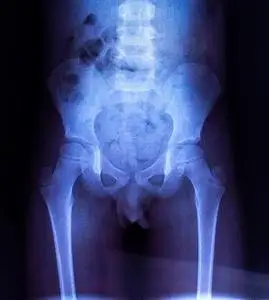

儿童骨盆 x 线检查照片